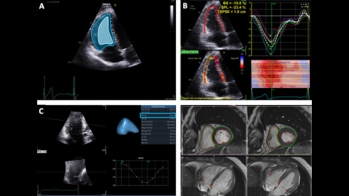

Différence entre amylose AL et ATTR, symptômes extra-cardiaques… Les signaux qui doivent conduire à suspecter une amylose revus par le Dr Antonin Trimaille et le Pr Nicolas Lamblin, dans le 1er épisode de la série “Amyloses cardiaques, les situations cliniques du cardiologue en formation”.